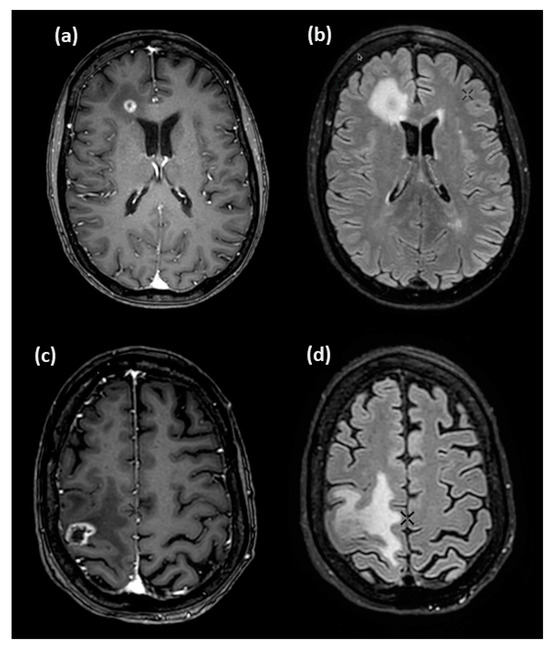

3.2. Dynamic Presentation of Concentrations and Counting Statistics

3.4. Assessment of Diagnostic Performance